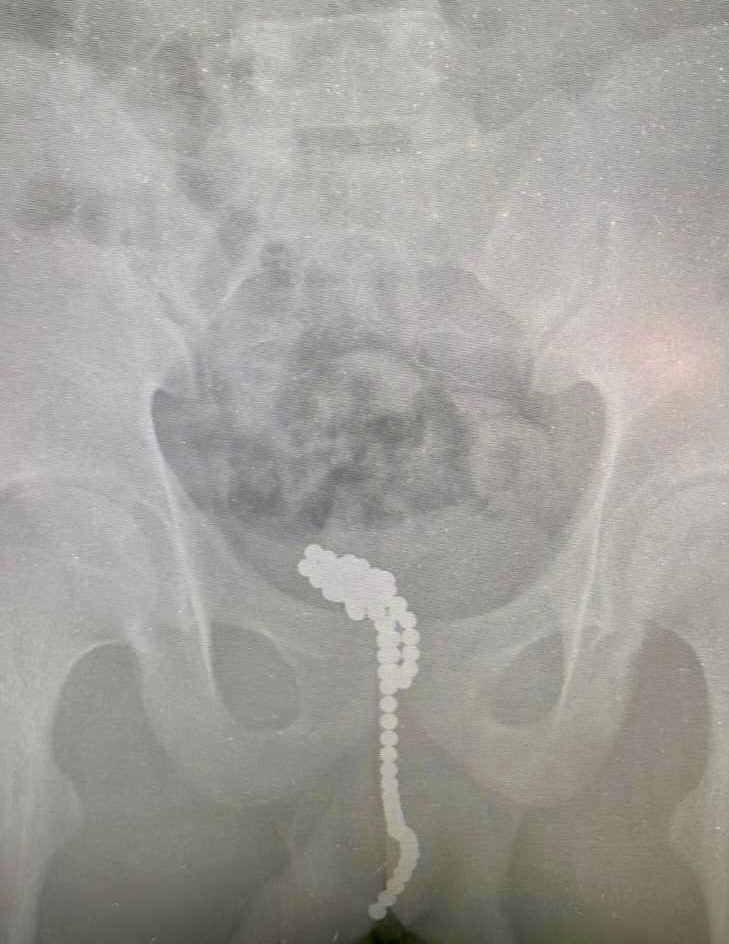

Врачи больницы в Люберцах достали из полового органа 13-летнего школьника около 50 магнитных шариков. Подросток обратился к медикам с жалобами на мочеиспускание. Об этом в понедельник, 1 июля, рассказала пресс-служба Минздрава Подмосковья. При осмотре подросток признался врачам, что засунул в свой пенис магнитные шарики. Медики не стали выяснять, как и почему он это сделал. «У маленького исследователя своего тела развилась острая задержка мочи. Чтобы мочевой пузырь не лопнул, детские урологи-андрологи катетеризировали его, а затем подготовили ребёнка к операции», — говорится в сообщении Минздрава. Магниты извлекли через небольшой разрез в мочевом пузыре. Последний рентген подтвердил, что инородных тел в мальчике больше не осталось. Сейчас с ним все хорошо — любопытный школьник выписан на амбулаторное наблюдение.

Магниты извлекли через небольшой разрез в мочевом пузыре. Последний рентген подтвердил, что инородных тел в мальчике больше не осталось.